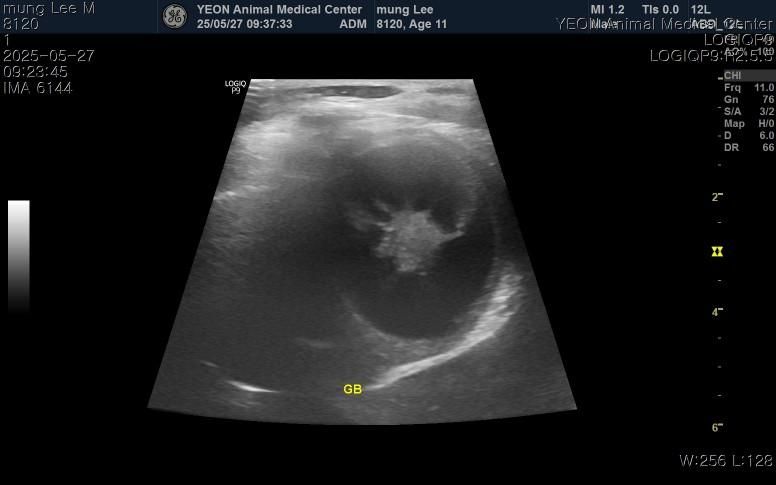

구토, 식욕저하, 기력저하로 내원해서 진료,검사 받아보니 염증, 간, 담낭 등 수치가 심하게 높다고 했고 빠른 입원치료와 담낭절제수술을 안내받았습니다.

그리고 십이지장에 크론병?도 의심된다고 하는데 담낭 치료와는 치료방법이 상극이어서 담낭 먼저 제거하고 스테로이드치료가 필요하다고 안내받았습니다.

담낭이 파열했을 가능성을 충분히 고려해야 하는 상태로 보이므로 비선택적 수술 즉, 반드시 수술해야 하는 상태 가능성이 높습니다. https://diamed.tistory.com/341 파열전에 수술하는것에 비해 사망 가능성이 높아진 상태이지만, 비선택적으로 반드시 수술해야 하는 상태로 판단됩니다. 주치의와 진솔한 대화 후 수술 진행하시기 바랍니다.